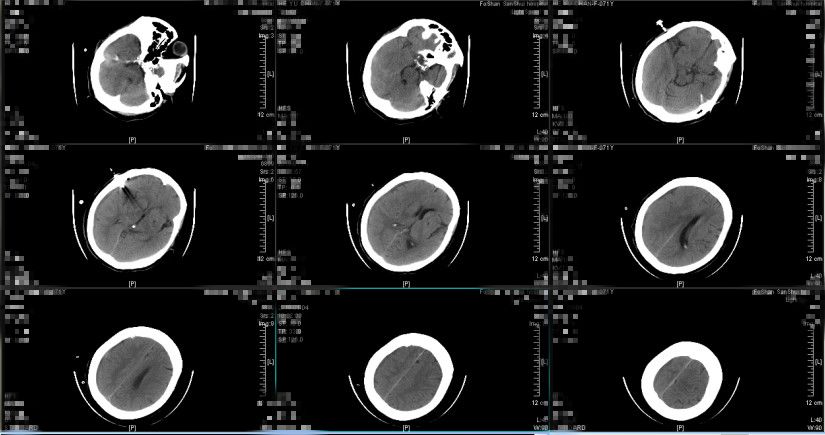

2019年1月29日门诊复查头颅CT(图11、图12)如下:提示亚急性硬膜下血肿已吸收,未见新发血肿形成。

图11

图12